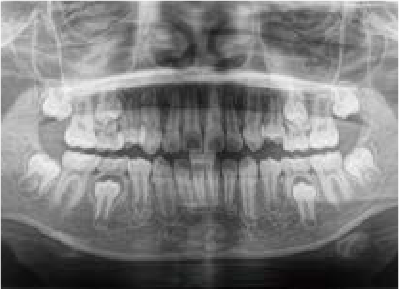

Before

歯がガタガタに並んでいて、前歯の真ん中の位置が少し左にずれていました。

奥歯が生えるためのスペースが足りず、永久歯が生えて来られない状況が確認できました。

また、飲み込むとき下くちびるに力が入ってしまうクセが見られ、お顔全体の成長が遅れている様子が確認できました。

治療を終えて

歯がきれいに生えるためのスペースをしっかり確保することができ、歯並びを乱していたお口のクセも改善されたため、奥歯が生えるスペースを確保することができました。

しっかり噛めるかみ合わせを作ることが、将来の健康につながるので「よく噛む」練習も続けてもらっています。

主訴・治療内容 歯がガタガタになってきたことに悩み、無料相談に来院されました。

治療期間 3年

費用 462,000円(税込)